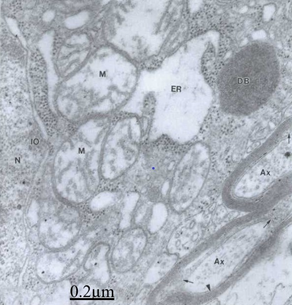

Electron microscopy images of astrocytes at low magnification show nerve cells charged of numerous lipofucsin granules (Figure 11). Besides, we report edematous and ischemic oligodendrocytes (Figure 12).25,26

Figure 12 Brain traumas, hematoma subdural. Severely edematous oligodendrocyte showing the nucleus (N) and lacunar enlargement of endoplasmic reticulum (ER), swollen mitochondria (M) and dense body (DB). The associated and degenerated myelinated axons show granular precipitation of axoplasm (Ax), and enlargement of periaxonal space (short arrow). The arrowhead indicates the axolemmal membrane.